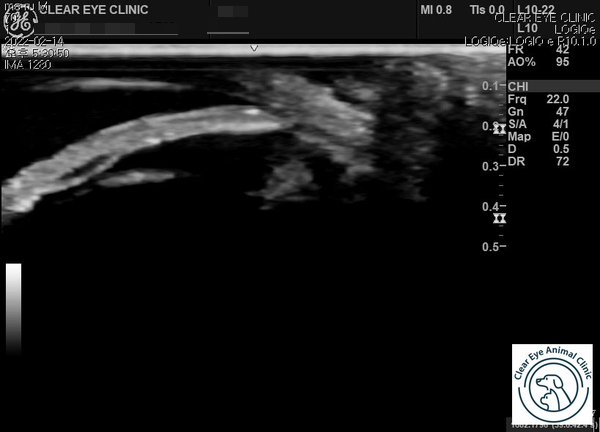

오른쪽 다리 거울과 초음파를 통해 눈 방수 배출 경로를 확인합니다.